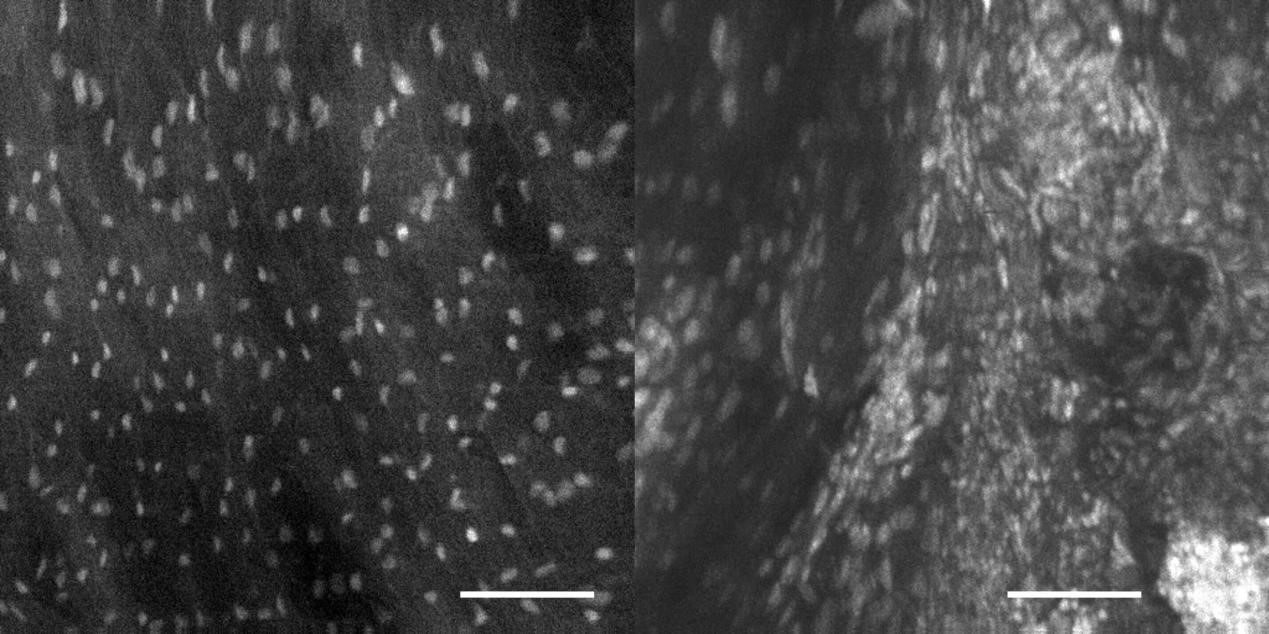

2、宫颈癌OptiScan成像

左:正常鳞状上皮;右:宫颈上皮肉瘤变。

注:0.05%吖啶黄溶液外用。Scale bar=100μm。